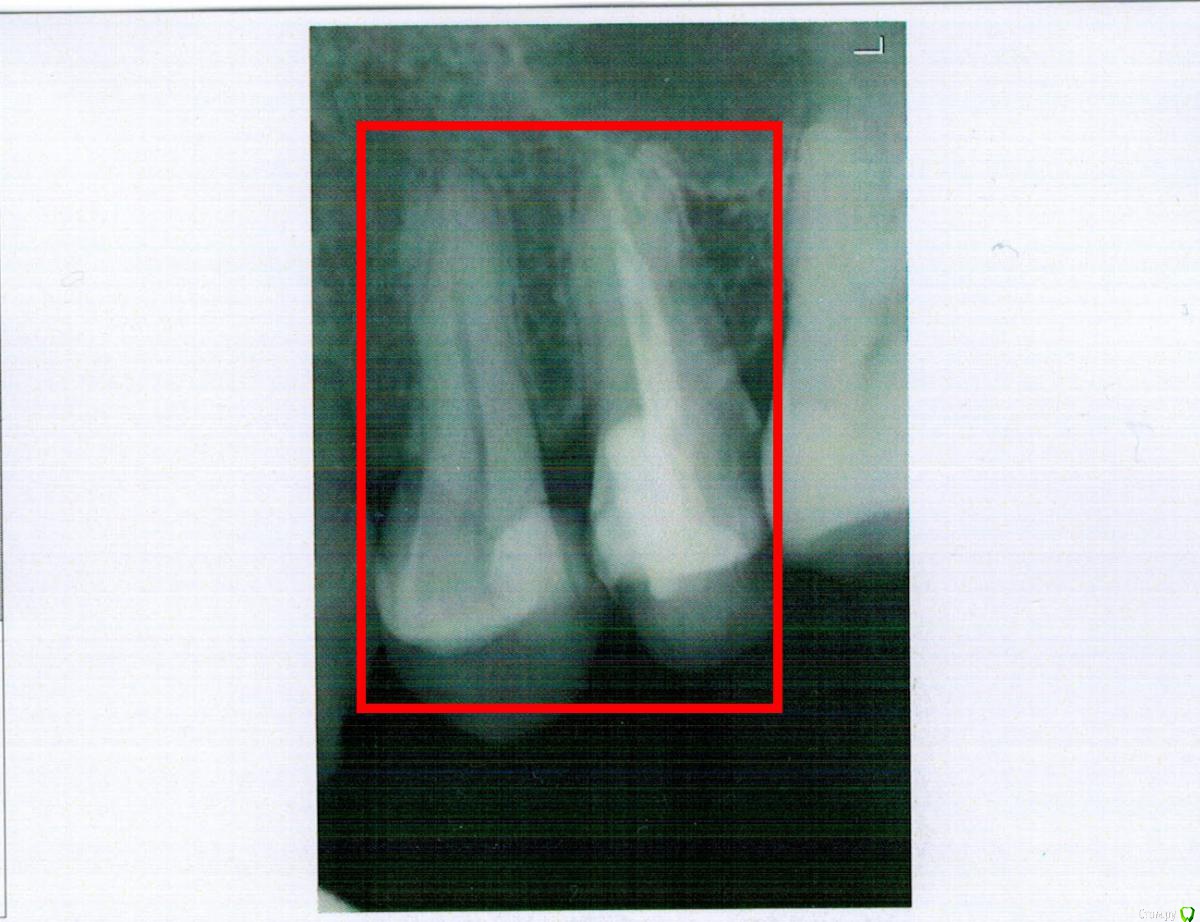

Роман79 Опубликовано 11 февраля, 2016 Поделиться Опубликовано 11 февраля, 2016 Добрый день! Прошу совета. Стоит ли ставить коронки на зубы (фото)?. Стоматолог предлагает ставить 2 коронки и говорит, что стенки тонкие. Заранее спасибо за ответы. Ссылка на комментарий

IvanK Опубликовано 11 февраля, 2016 Поделиться Опубликовано 11 февраля, 2016 Здравствуйтена 5ку точно 3 Ссылка на комментарий